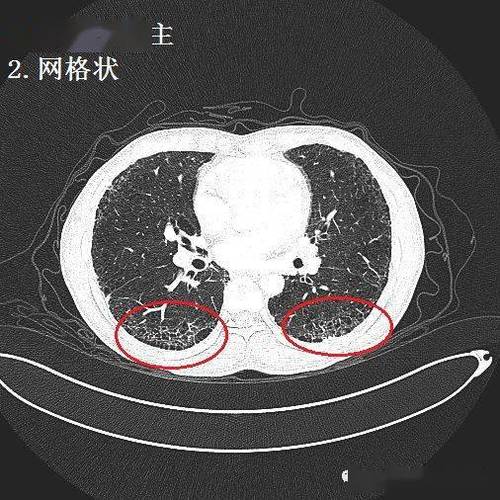

间质性肺炎的典型图谱,最全解析!

极易漏诊的间质性肺炎,从ct上怎么看?

间质性肺炎ct表现

间质性肺炎ct

间质性肺炎ct图片

间质性肺炎ct图片特点

间质性肺炎早期ct图片